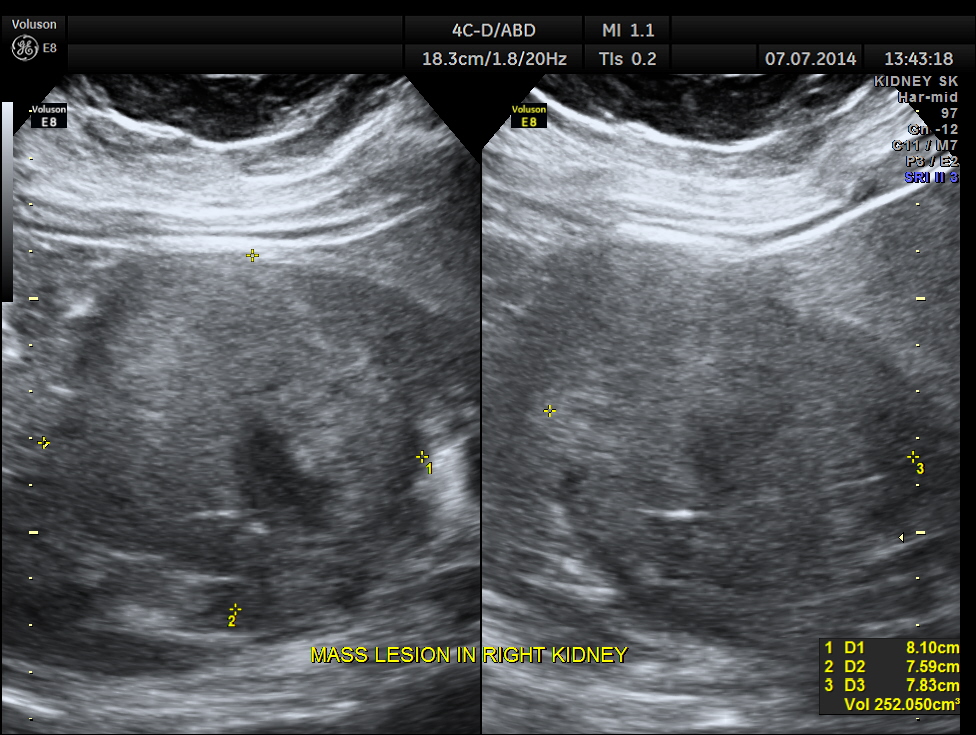

The right kidney is shown below. A solid mass is seen in the lower pole region.

The mass measurements are given below.